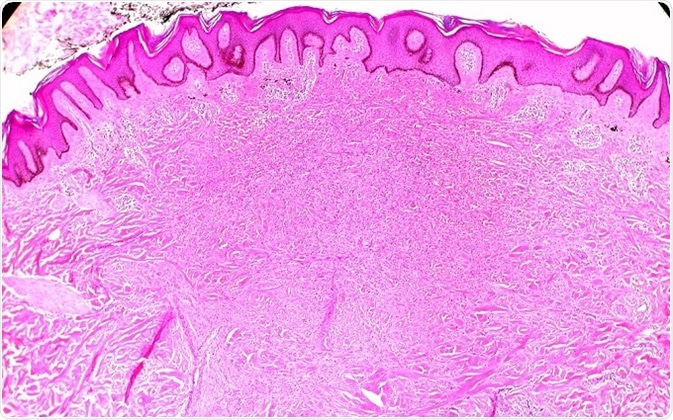

Histology of Dermatofibroma. ©Ed Uthman/ flickr.com

A dermatofibroma arises from oval spindle cells or histiocytes, with a slightly rough surface. It grows slowly, and is usually noticed when it is about 0.5 - 1 cm. It appears to be a darker firm nodule, plaque or papule on the skin, and this firmness is quite distinctive. They typically appear to have one shade of color, which ranges from reddish-brown or dark brown through pink to tan. They are raised above skin level in most cases, and appear hyperkeratotic or acanthotic. The tumor is non-capsulated, with ill-defined borders, and it may extend into the subcutaneous fat. These tumors are the firmest of the benign skin nodules, which is an important clinical feature.